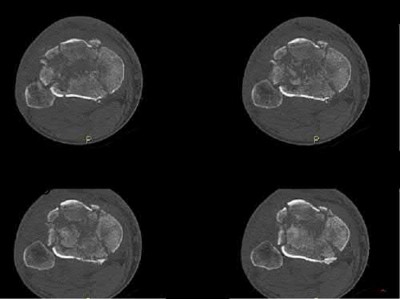

A 28-year-old male sustains a severe hyper-dorsiflexion injury to his ankle in a motor vehicle accident, resulting in a Hawkins Type III talar neck fracture. Which of the following arteries provides the predominant blood supply to the body of the talus, placing it at significant risk for avascular necrosis in this injury?

Options:

- Artery of the sinus tarsi

- Anterior tibial artery

- Dorsalis pedis

- Artery of the tarsal canal

- Peroneal artery

Correct Answer: Artery of the tarsal canal

Explanation:

The artery of the tarsal canal, which is a branch of the posterior tibial artery, provides the dominant blood supply to the talar body. In a Hawkins Type III fracture (talar neck fracture with subtalar and tibiotalar dislocation), the blood supply from the artery of the tarsal canal, the artery of the sinus tarsi, and capsular vessels are disrupted, leading to an avascular necrosis (AVN) rate approaching 100%.